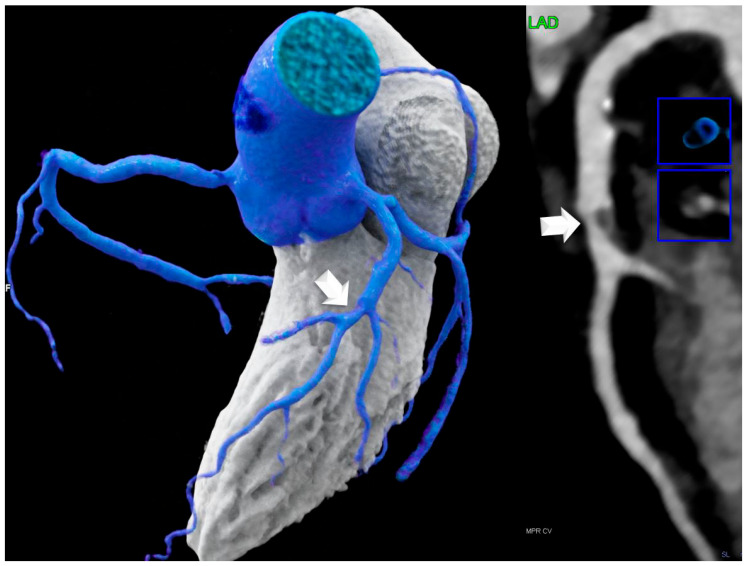

背景:虽然心外膜脂肪组织(EAT)是已知的不良心血管结局的预测因子,但心房间隔脂肪瘤性肥厚(LHIS)是由代谢活性脂肪(如棕色脂肪组织)组成的,它可能发挥不同的作用。本研究使用CTA研究LHIS患者的冠状动脉粥样硬化概况,并与倾向评分匹配的对照组进行比较。方法:共纳入142例患者(LHIS组71例,对照组71例),对年龄、性别、BMI和主要CV危险因素(匹配水平)进行倾向评分匹配。结果:平均年龄60.9岁+/- 10.6岁,女性9例(6.3%),平均BMI为28.04 kg/m2 +/- 4.99。LHIS患者HRP患病率明显低于对照组(21.1%比40.8%,p < 0.011),而CAC (p = 0.827)和CADRADS (p = 0.329)差异无统计学意义,在阻塞性疾病发生率上无统计学差异。脂质组(胆固醇、低密度脂蛋白、高密度脂蛋白、甘油三酯)和他汀类药物摄取率没有差异。结论:LHIS患者HRP患病率低于对照组,冠状动脉狭窄严重程度和CAC评分差异无统计学意义。临床相关性:LHIS可作为逆转CV风险的成像生物标志物。

Background: While epicardial adipose tissue (EAT) is a known predictor of adverse cardiovascular outcomes, lipomatous hypertrophy of the interatrial septum (LHIS) is composed of metabolically active fat such as brown adipose tissue, which may exert a different effect. This study investigates the coronary atherosclerosis profile in patients with LHIS using CTA, compared with a propensity score-matched control group. Methods: A total of 142 patients were included (n = 71 with LHIS and n = 71 controls) and propensity score-matched for age, gender, BMI, and the major CV risk factors (matching level, <0.05). CTA imaging parameters included HRP, coronary stenosis severity (CADRADS), and CAC score. Results: The mean age was 60.9 years +/- 10.6, there were nine (6.3%) women, and the mean BMI is 28.04 kg/m2 +/- 4.99. HRP prevalence was significantly lower in LHIS patients vs. controls (21.1% vs. 40.8%; p < 0.011), while CAC (p = 0.827) and CADRADS (p = 0.329) were not different, and there was no difference in the obstructive disease rate. There was no difference in lipid panels (cholesterol, LDL, HDL, TG) and statin intake rate. Conclusions: HRP prevalence is lower in patients with LHIS than controls, while coronary stenosis severity and CAC score are not different. Clinical relevance: LHIS may serve as imaging biomarker for reversed CV risk.